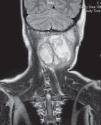

Se realiza una tomografía computarizada cervical (fig. 1), donde se observa una lesión quística de contenido heterogéneo con septos en su interior, con paredes bien definidas y sin vascularización interna ni periférica, que indica el diagnóstico de linfangioma sobreinfectado. Así mismo se evidencia afectación ósea adyacente en los arcos posteriores de C2 y C3. La resonancia magnética (fig. 2) permite la visualización de la extensión de la masa hasta espacio epidural, con desplazamiento de la médula espinal. Para su estudio etiológico, se realiza la punción aspiración de la tumoración, evidenciándose contenido lechoso purulento, presentando un crecimiento positivo cultivo a Staphylococcus aureus compatible con material linfático sobreinfectado. El estudio histopatológico de la muestra evidenció tejido necrótico-hemorrágico sin presencia de atipias. Se realizó un drenaje quirúrgico de la lesión y se inició antibioterapia empírica por vía intravenosa con evolución favorable.